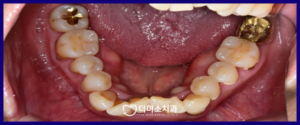

먼저 구강 내를

확인해 보았더니

보험이 되는 G.I 재료로

치경 부위가 수복돼 있었으며,

환자분 말씀대로

일부 파절된 곳도 있었으며,

기포로 인한 구멍, 2차 우식,

맞지 않는 치은연 수복물로 인해

치은 발적이 있는 곳도 확인되었는데요.

레진으로 치경부 마모증 치료를

마무리 한 구강 내 사진인데요.

처음 내원하셨을 때보다

훨씬 더 심미적으로 변한 모습을

확인할 수 있었습니다.